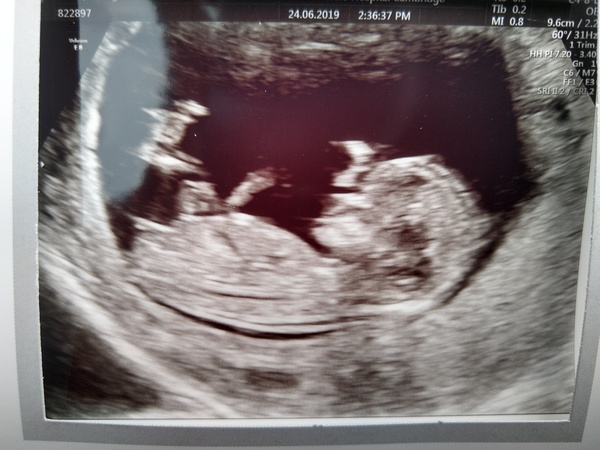

Had my 12 week scan today and all looking good 😁 although placenta has formed anterior which I'm a little sad about as was hoping for prosterior this time but just happy baby is happy and healthy. DD moved forward 5 days to 1st January 😅

I have my suspicions over sex but interested to hear what others think?

Cat definitely looks like a girl nub to me!

Oh @splishandsplash that is one beautiful scan photo! I would have to say boy aswel going on the scan!! Congratulations x

@CatRash another beautiful scan photo!! I agree with missmonkeypenny, defo looks like a girl to me aswel!!

Congrats @CatRash agree with @Missmonkeypenny - definitely looks like a girl to me too!

@CatRash same due date at me! Unless they try and change it tomorrow! Another vote for girl judging by the skull

Thanks @Missmonkeypenny, @mynameisMrG, @megganonion and @Bentley111 - I thought girl too and that's what ramzi theory on my 8 week scan indicated too.